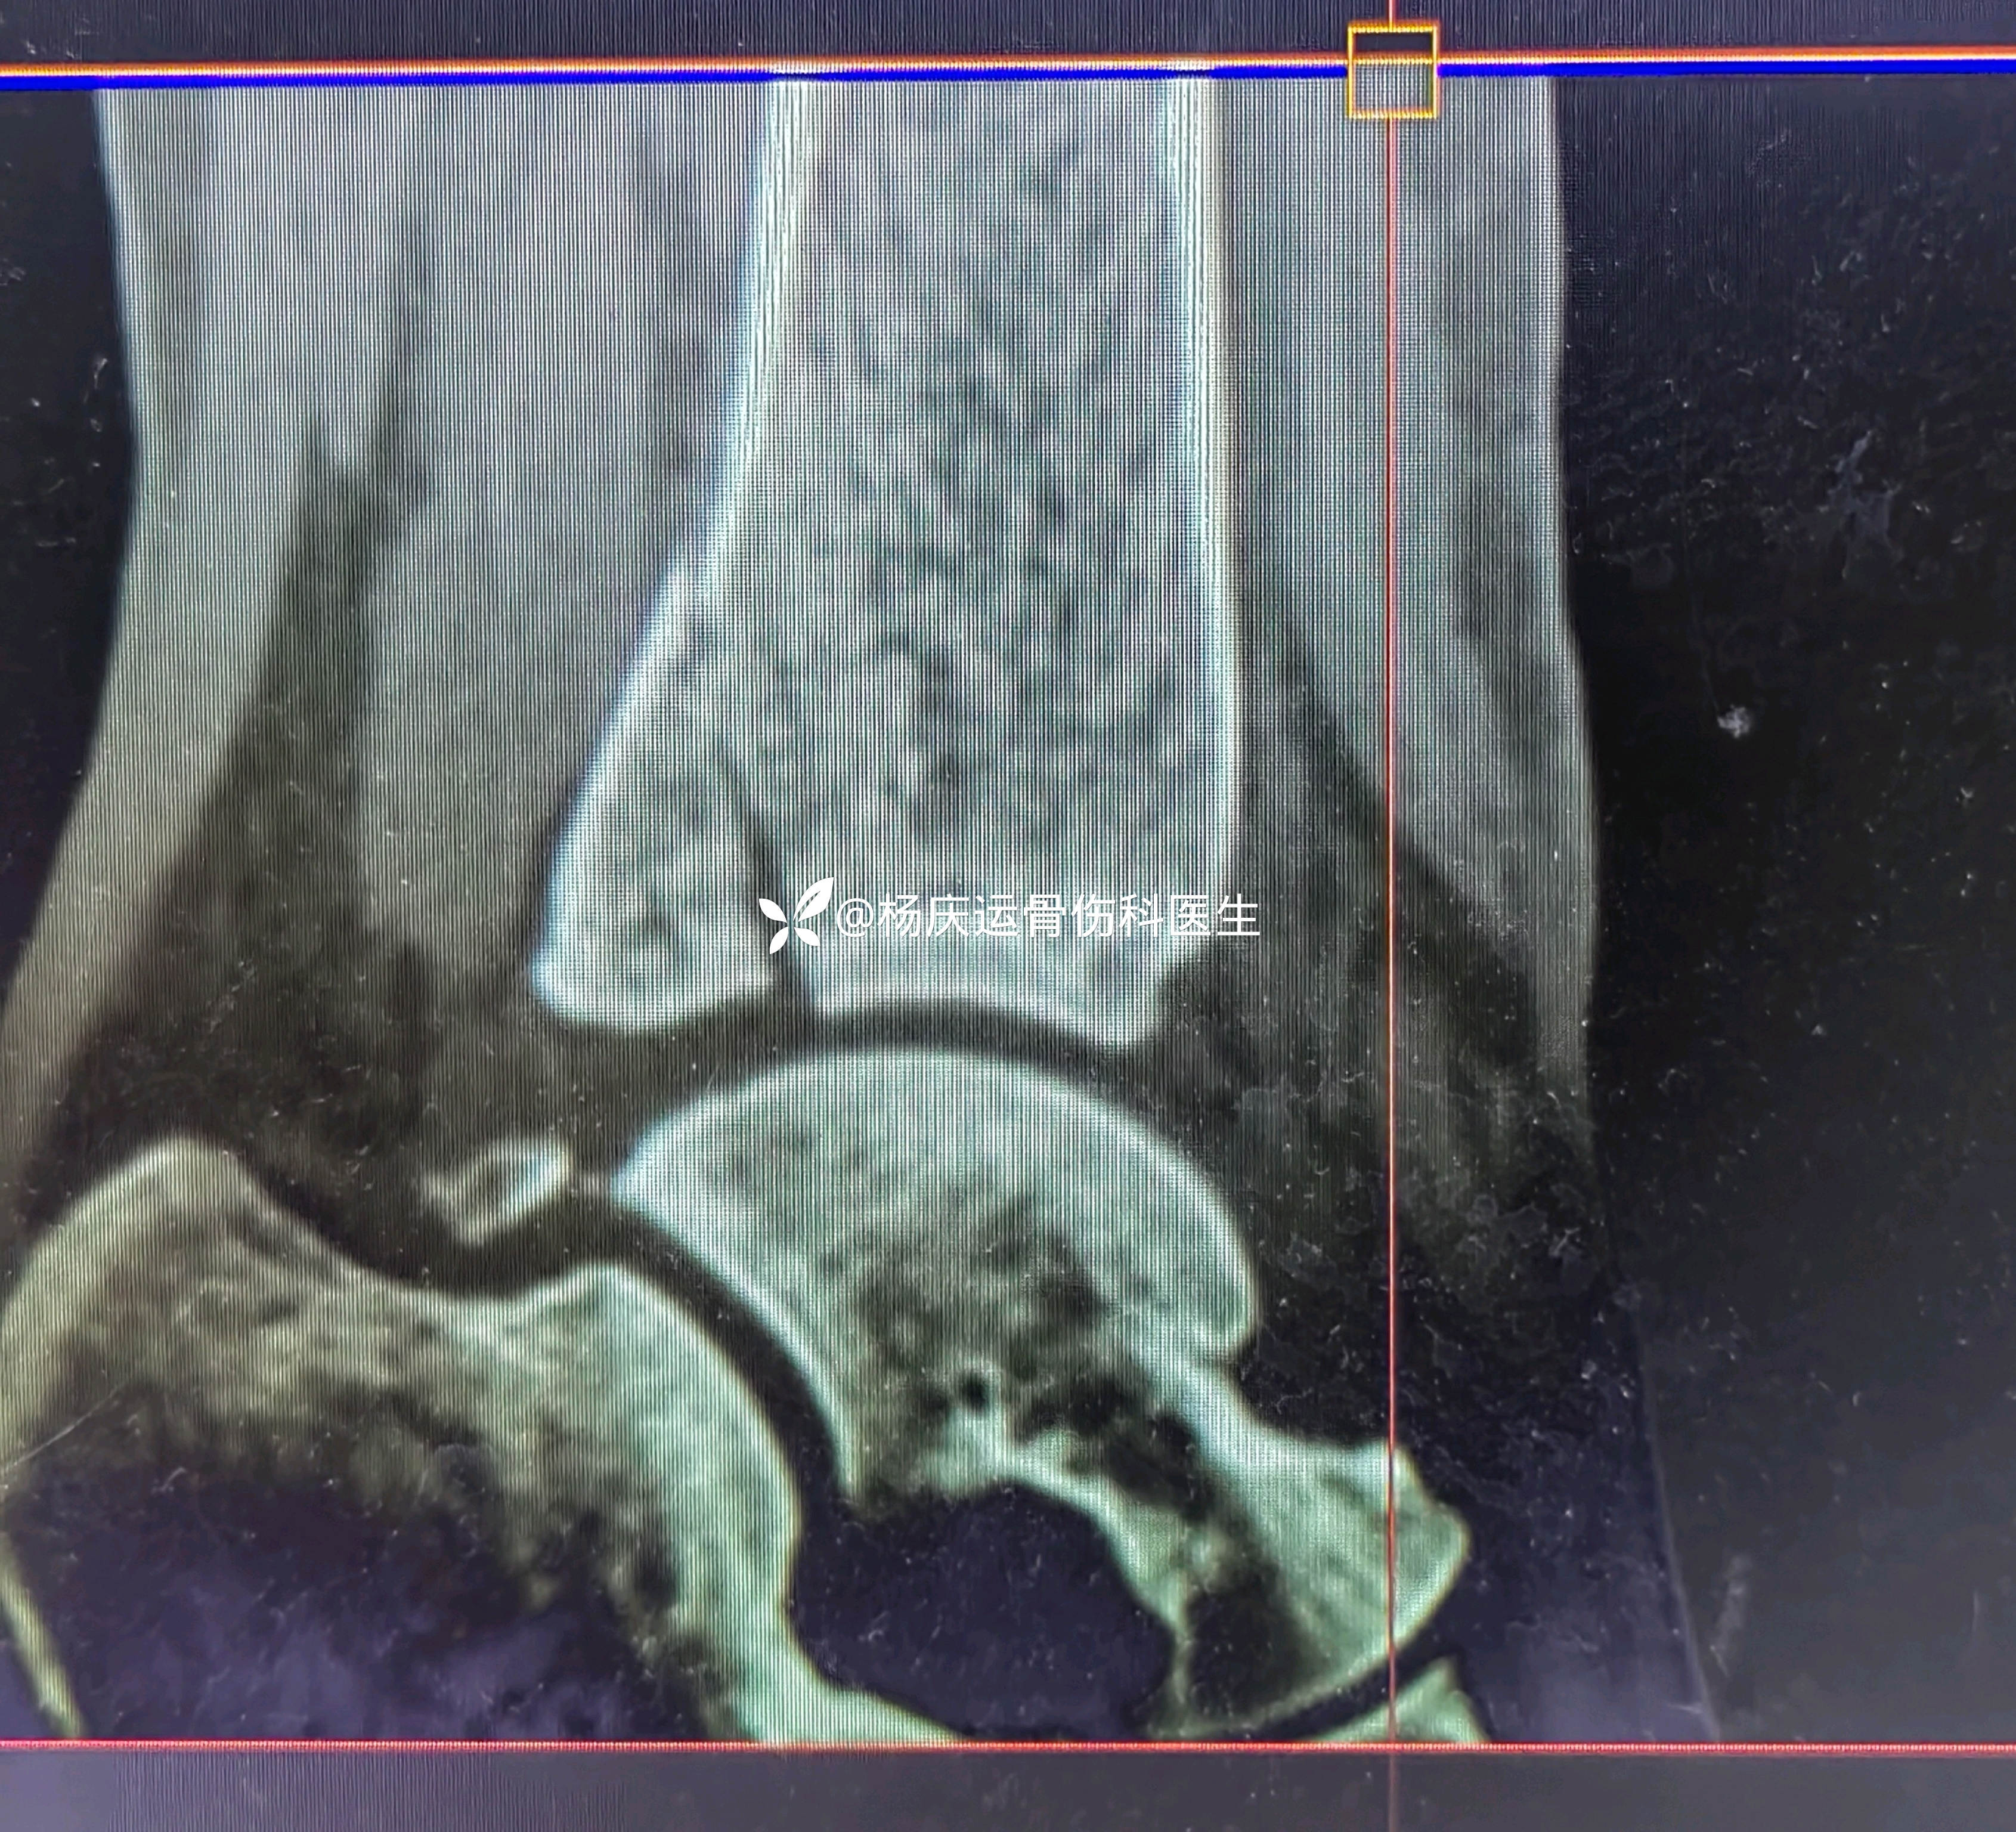

复位后

3天复查CT

关节面台阶约1.0mm